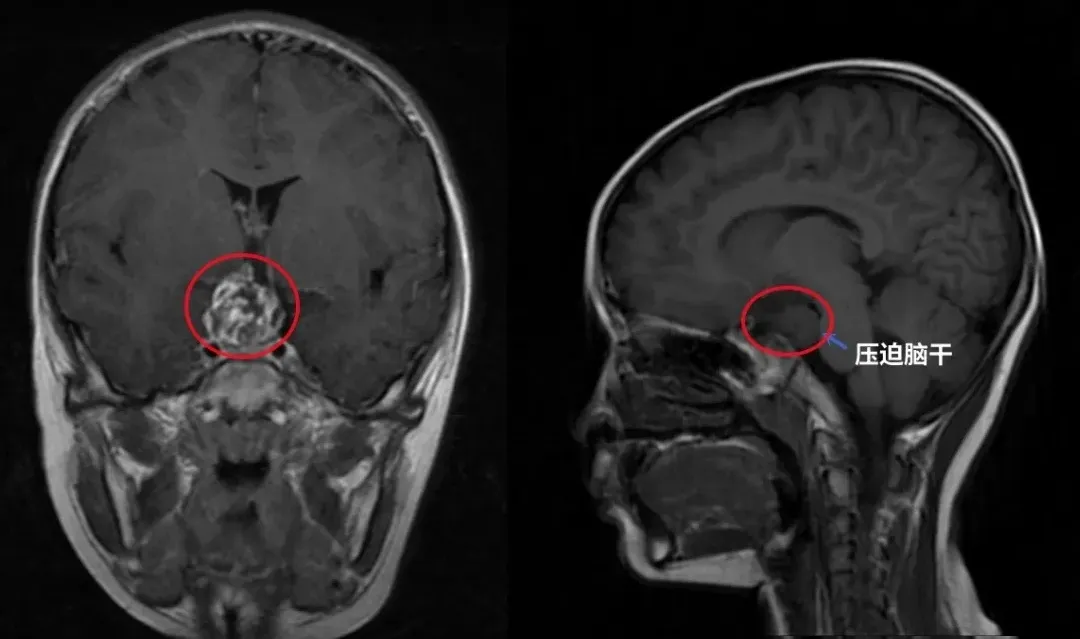

術(shù)前核磁影像

一家人都懵了,本以為只是個(gè)很簡(jiǎn)單的小問(wèn)題,完全沒(méi)有心理準(zhǔn)備。這時(shí)他們才反應(yīng)過(guò)來(lái)前幾個(gè)月孩子出現(xiàn)的無(wú)端嘔吐可能就是腫瘤壓迫到腦組織引發(fā)的癥狀。

2024年2月底,3歲男孩浩浩因?yàn)楹竽X部不慎遭受撞擊偶然查出腦干占位性病變。發(fā)現(xiàn)腫瘤后,浩浩并沒(méi)有任何不適的感覺(jué),只是父母發(fā)現(xiàn)發(fā)現(xiàn)孩子右手相較之前力氣下降,行走時(shí)右腳力氣不足。這種情況也很常見(jiàn),由于處于成長(zhǎng)期的兒童表達(dá)癥狀還較為困難,因此很多兒童顱內(nèi)腫瘤是被偶然發(fā)現(xiàn)的。

▼浩浩術(shù)前影像

3歲男孩——腦干膠質(zhì)瘤